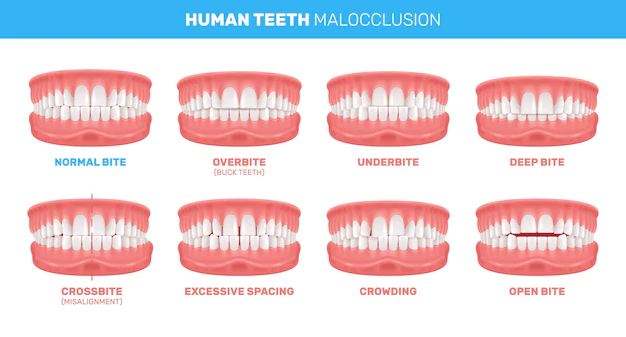

In case you are suffering from crooked teeth and poor bite then this is the case of Malocclusion. When we talk about bite we refer to the alignment of upper and lower teeth. When you observe your teeth and see that the upper portion is slightly ahead of the lower then you have a normal bite. Point to be noted here is that no one has a perfect bite.

The most spot on symptom is tooth being crooked or moving out. Some people suffer from overbite which means that the upper teeth are sticking out. On the other hand certain people suffer from under bite which means the lower front teeth sticks out more than the upper ones.